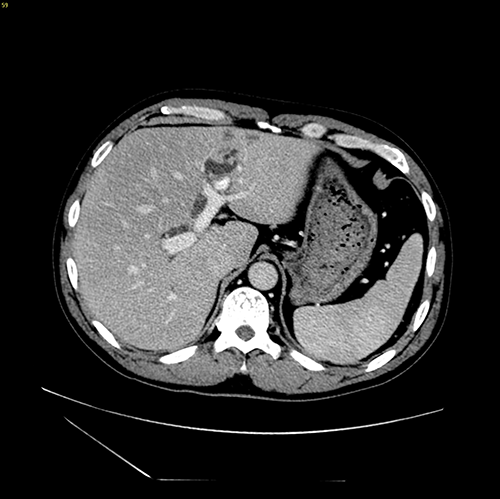

左肝胆管结石--腹腔镜左肝叶切除